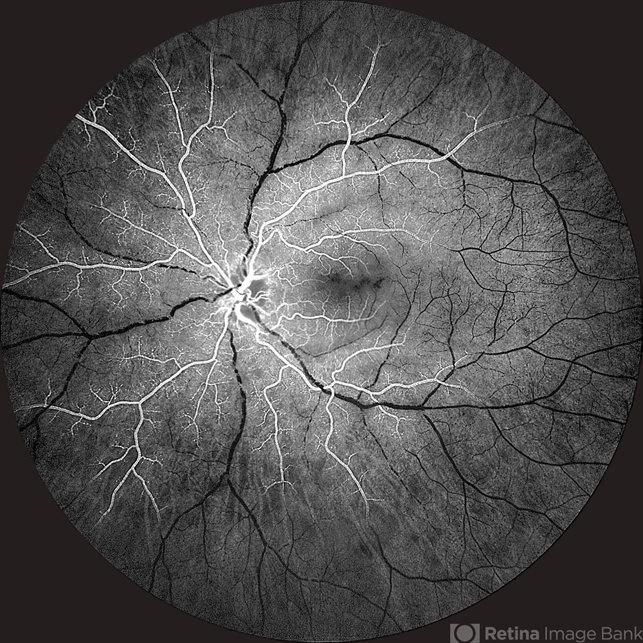

- CRAO, takayasu arteritis, calcified drusen

- Fundus fluorescein angiography image of a young girl with diagnosed Takayasu arteritis who presented with complains of diminished vision in both eyes. FFA shows complete absence of venous filling with segmented blood column secondary to CRAO with peripheral avascular area.